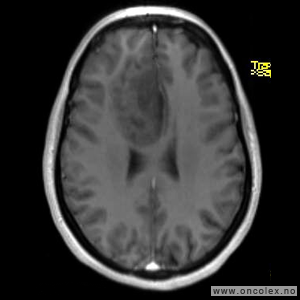

MR er det viktigste diagnostiske hjelpemiddel for å påvise hjernesvulster. Ofte gjøres det først en CT av hjernen, men CT-undersøkelsen har klare begrensninger når det gjelder fremstilling av hjernesvulster. CT- eller MR-angiografi gjøres av og til for å kartlegge blodåresystemet i hjernen og eventuelle blodårer i og rundt en svulst.

Glioblastomer

Glioblastom er den vanligste hjernesvulsten hos voksne, og cirka 220 norske personer får denne diagnosen hvert år. Samtidig er det en av de mest aggressive svulsttypene hvor i praksis alle pasienter på ett eller annet tidspunkt vil oppleve tilbakefall. Cirka 60 % av pasientene er menn og halvparten av pasientene er over 60 år. Behandling vil oftest være en kombinasjon av operasjon, strålebehandling og cellegift. For en del pasienter kan det være aktuelt å delta i studier med utprøving av ny behandling.